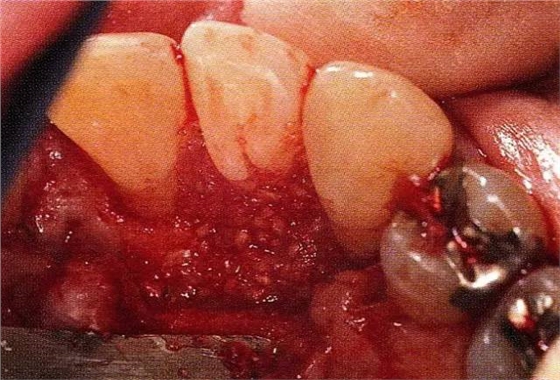

▲圖7-4術(shù)后1年2個(gè)月再翻開看的情況。與圖7-1的骨缺損狀態(tài)相比可知形成了臨床性骨再生。

▲圖7-5此狀態(tài)下,左下5的遠(yuǎn)中存在牙槽骨不平整,因此進(jìn)行了骨修整。同時(shí),將骨膜留存,進(jìn)行了齦瓣根尖側(cè)移動(dòng)術(shù),去除了牙周袋。